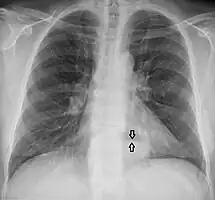

A large hiatal hernia on chest X-ray marked by open arrows in contrast to the heart borders marked by closed arrows

This hiatal hernia is mainly identified by an air-fluid level (labeled with arrows). -